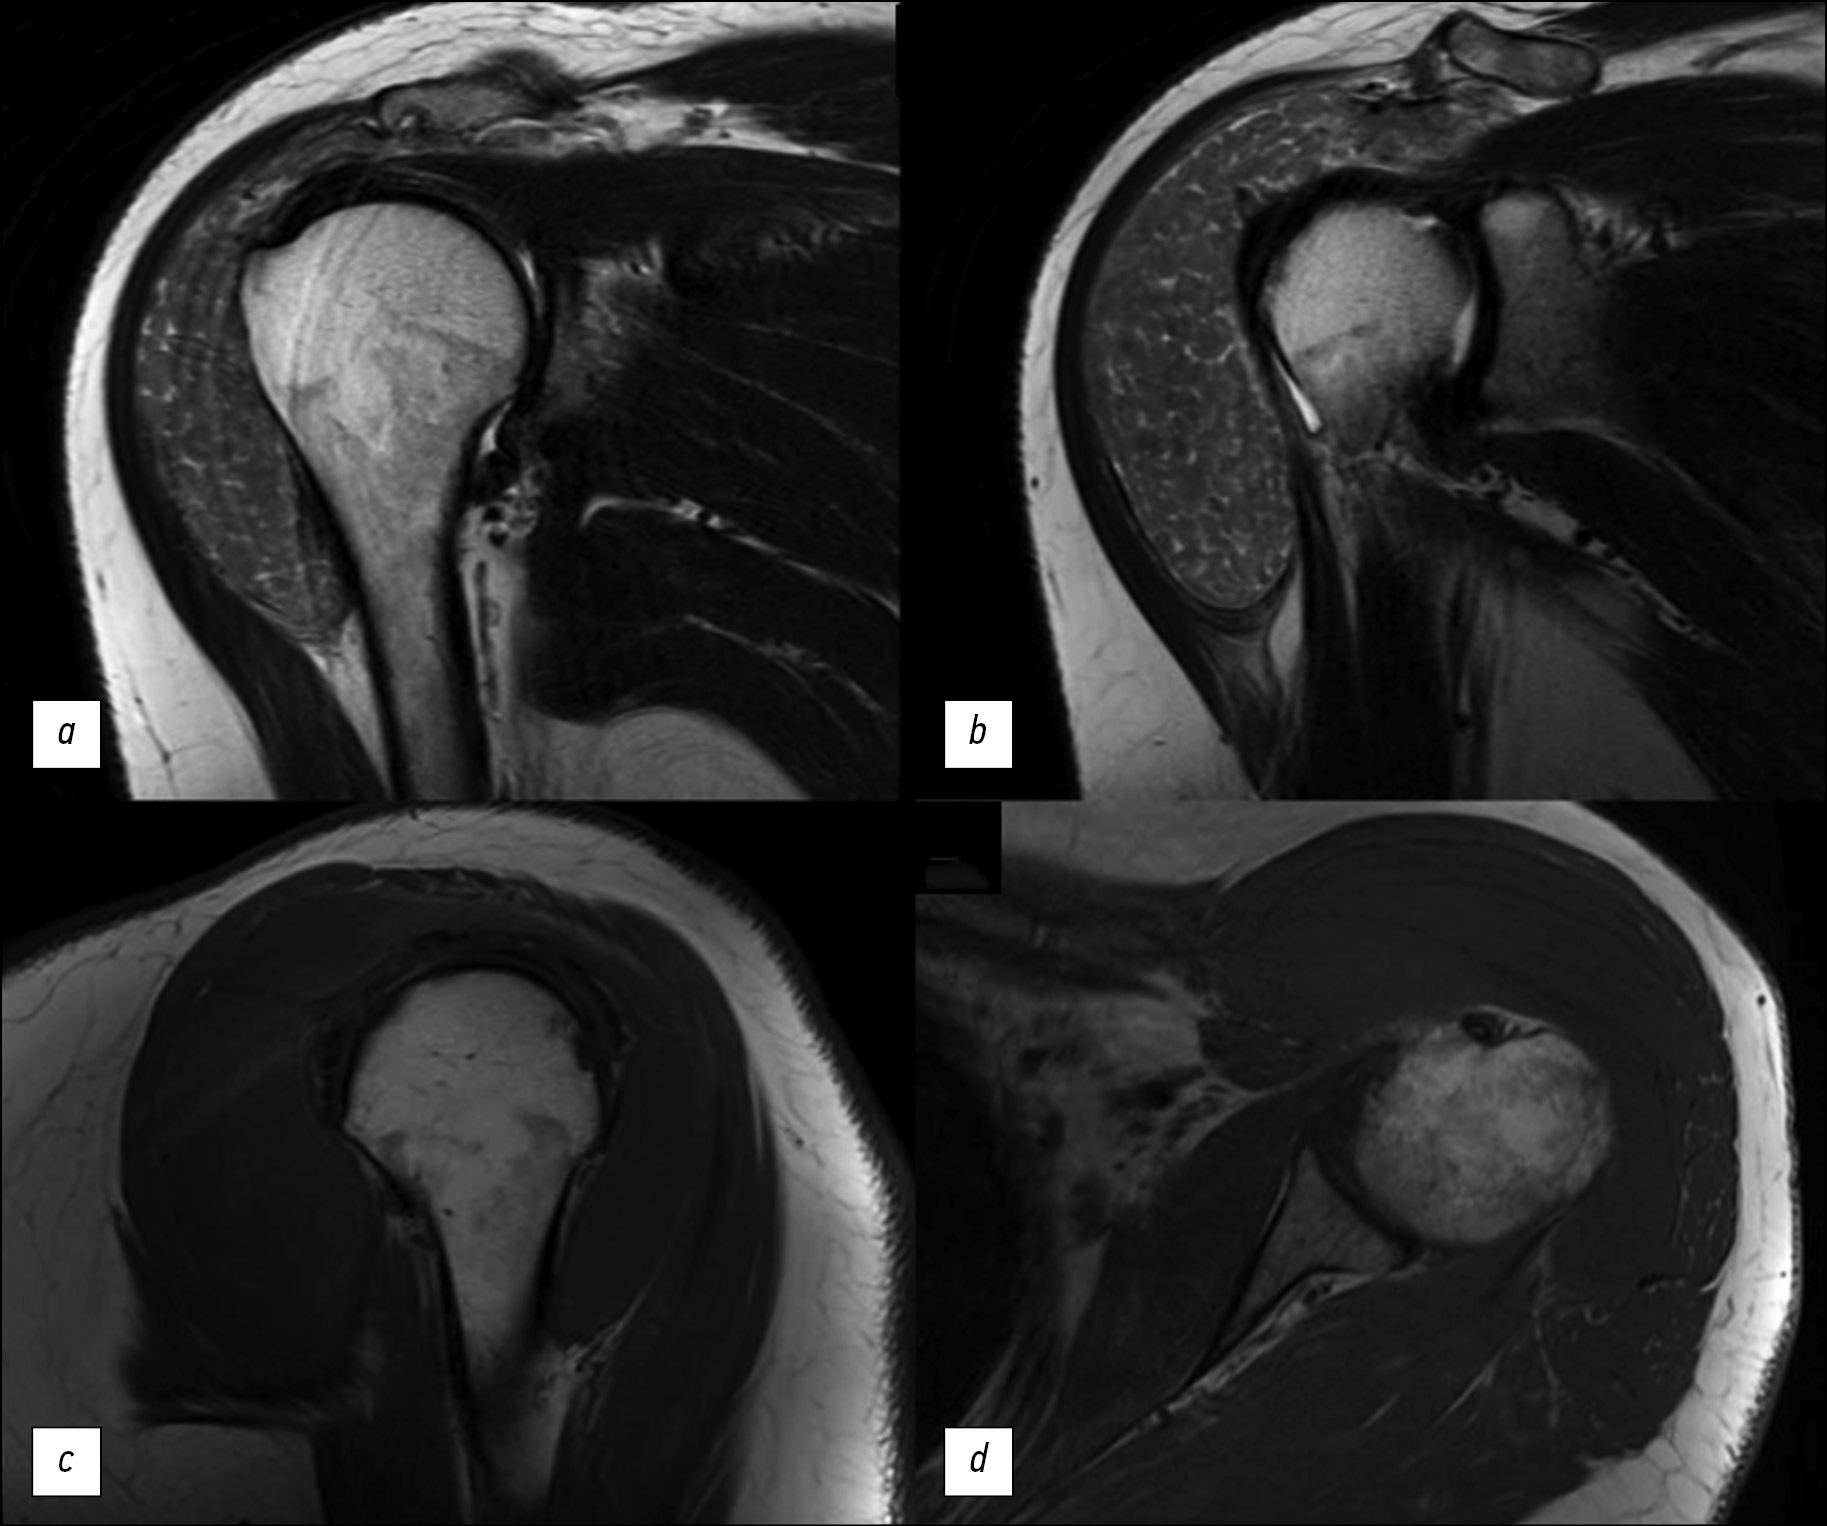

类风湿性关节炎患者肩关节磁共振成像(MRI)上的米粒体症状是一种罕见但特殊的发现。其特征是关节滑液、滑膜囊或滑膜鞘中出现多个圆形小结构。这些结构彼此相似,就像米粒一样。米粒体的成因至今不明。据推测,米粒体是因类风湿性关节炎或其他炎症性关节疾病患者滑膜微梗塞而形成的。在临床上,米粒体的存在可能会使患者感到疼痛。然而,情况并非总是如此。在放射诊断方法中,磁共振成像在检测米粒体方面发挥着主导作用。

本文介绍一例在肩关节磁共振成像中发现该症状的临床病例。该症状是在一名有长期类风湿性关节炎病史的患者身上发现的。患者因左肩部无痛性增大而就医。对左肩关节进行了电子计算机断层扫描(CT)和磁共振成像检查。医生通过这些检查发现了,米粒体症状是基础疾病的一种表现形式。这些检查有助于确定进一步的治疗策略。